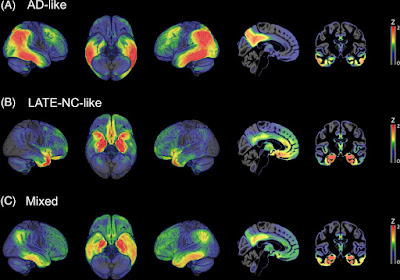

MRI or fluorodeoxyglucose (FDG)-positron

emission tomography (PET) findings

Your health care provider may look for changes in the

brain that can be caused by LATE. These can include signs of brain

shrinkage (atrophy) and thinning of the parts of the brain responsible for

memory formation. These changes can be seen on MRI examination and on

autopsies. Thinning seems to be a stronger indicator of how severe the disease

is compared with atrophy.